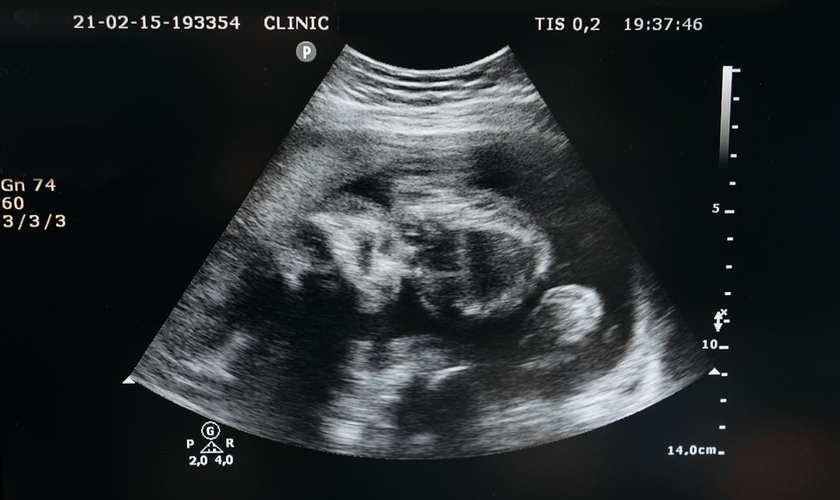

Mudança no Código Civil reconhece personalidade legal ao feto. (Foto: Pavel Danilyuk / Pexels)